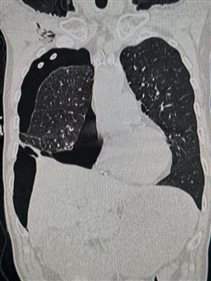

术后